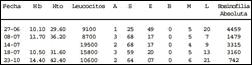

Examenes auxiliares:

Bilirrubina total 1.42 mg/dl. Bilirrubina directa 0.54 mg/dl. Bilirrubina indirecta 0.88 mg/dl. Proteínas totales 6.76 gr%. Albúmina 4.22 gr%. Globulina 2.54 gr%. TGO 240 U/L. TGP 627 U/L. F. Alcalina 107 U/L. Protrombina 11.9 100% INR 0.90. Amilasa sérica 49 U/L. Antígeno carcinoembrionario 1.42 ng/ml (0-5). Alfa feto proteína 1.53 ng/ml (0-10). VIH1-VIH2 (ELISA) no reactivo. VDRL No reactivo. AgHBs No reactivo. Glicemia 101 mg/dl. Creatinina 0.63 mg/dl. Western blot Hidatidosis Negativo. Coproparasitólogico seriado negativo.

Ecografía Abdominal: Masa heterogénea en el lóbulo derecho hepático de 13 cm de diámetro que parece desplazar a la vesícula(Fig 1).

Fig 1.- Ultrasonografía: Masa heterogénea de 132 mm

en el lóbulo derecho del hígado.

Evolución: Es intervenida quirúrgicamente el 5 de julio con la presunción diagnóstica de hematoma hepático subcapsular de etiología a determinar. Se encontró hematoma hepático subcapsular de aproximadamente 800 cc en los segmentos 6, 7 y 8, el cual fue drenado. Posterior al evento quirúrgico persistió la hipereosinofilia y se obtuvo el resultado positivo de la Doble Difusión del Arco 2 compatible con fasciolosis. Recibió tratamiento con triclabendazol 10 mg/Kg por dos dias, evolucionando satisfactoriamente y con caida en los valores de eosinofilia y serología. Actualmente asintomática.

La anemia es común, pero usualmente no severa. Se reportan leucocitosis de hasta 43,000 y velocidades de eritrosedimentación de 165 para la fase aguda, normal para la latente y normal o moderadamente alta para la fase crónica. Las pruebas de función hepática se incrementan levemente a excepción de la fostasa alcalina en la fase aguda a diferencia de la fase crónica en la que la ictericia e hiperbilirrubinemia se hacen prominentes (3-7,10).